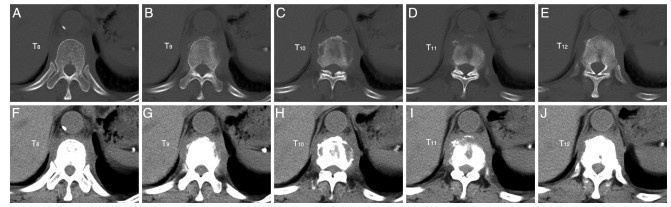

• This article reports a rare case of elderly thoracic vertebral multifocal eosinophilic granuloma (EG). The patient, a 66-year-old male, presented with "low back and waist pain accompanied by fatigue for over two years, and worsening for three months." After treatment with glucocorticoids combined with immunosuppressive conservative therapy, the clinical manifestations and laboratory tests improved. Pathological biopsy showed the disappearance of granulomatous tissue. Subsequently, due to the occurrence of compression fractures in the affected area, surgical treatment was carried out. This suggests that the treatment of glucocorticoids combined with cyclophosphamide is feasible for adult patients with multi-site bone eosinophilic granuloma.